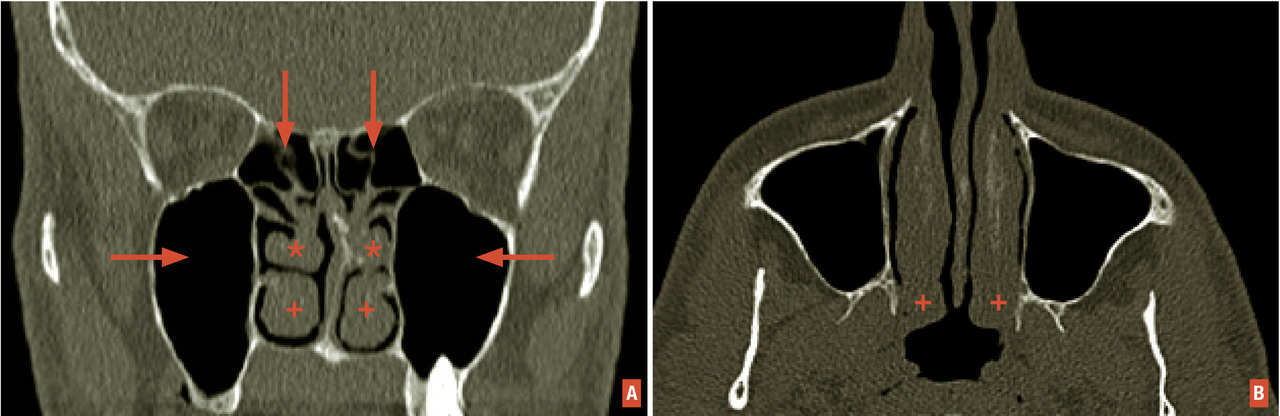

En tomodensitométrie, les polypes se traduisent par des opacités touchant les deux masses latérales de l’ethmoïde (fig. 1 ). Sur le plan biologique, la polypose nasale se caractérise par une inflammation chronique à éosinophiles de type Th2, mais non allergique. Elle s’associe parfois à un asthme et une intolérance à l’aspirine et aux anti-inflammatoires non stéroïdiens (syndrome de Widal).

En tomodensitométrie, les polypes se traduisent par des opacités touchant les deux masses latérales de l’ethmoïde (

Le dysfonctionnement nasal chronique d’une allergie aux acariens peut se rapprocher de celui d’une rhinite non allergique à éosinophiles ou d’une polypose nasale mais la fibroscopie nasale ne trouve pas de polypes francs des méats moyens ou des fentes olfactives. Elle objective seulement un aspect œdémateux, parfois même pseudo- polypoïde, de la tête ou du bord libre des cornets moyens, associé à une hypertrophie blanche, rouge ou lilas des cornets inférieurs, par ailleurs tapissés de sécrétions séreuses ou muqueuses qui peuvent s’accumuler sur le plancher nasal. Une tomodensitométrie doit alors compléter la démarche diagnostique. Dans la rhinite chronique aux acariens, les masses latérales de l’ethmoïde et les sinus paranasaux montrent une radiotransparence normale alors que l’essentiel des signes pathologiques sont retrouvés au niveau du nez respiratoire (qui ne fait actuellement l’objet d’aucune description dans les comptes-rendus radiologiques) [fig. 2 ]. C’est donc la concordance des signes nasofibroscopiques et tomodensitométriques qui contribue au diagnostic des rhinites respiratoires chroniques. L’origine allergique, toujours recherchée, n’est cependant pas systématiquement retrouvée.7

Le dysfonctionnement nasal chronique d’une allergie aux acariens peut se rapprocher de celui d’une rhinite non allergique à éosinophiles ou d’une polypose nasale mais la fibroscopie nasale ne trouve pas de polypes francs des méats moyens ou des fentes olfactives. Elle objective seulement un aspect œdémateux, parfois même pseudo- polypoïde, de la tête ou du bord libre des cornets moyens, associé à une hypertrophie blanche, rouge ou lilas des cornets inférieurs, par ailleurs tapissés de sécrétions séreuses ou muqueuses qui peuvent s’accumuler sur le plancher nasal. Une tomodensitométrie doit alors compléter la démarche diagnostique. Dans la rhinite chronique aux acariens, les masses latérales de l’ethmoïde et les sinus paranasaux montrent une radiotransparence normale alors que l’essentiel des signes pathologiques sont retrouvés au niveau du nez respiratoire (qui ne fait actuellement l’objet d’aucune description dans les comptes-rendus radiologiques) [